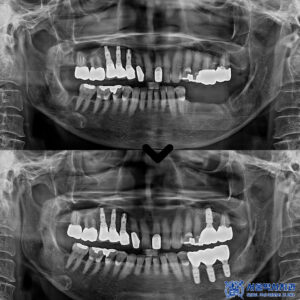

성남치과 남편 소개로 왔어요. 골다공증 환자분 뼈이식을 포함한 어금니 무절개 임플란트 사례

성남치과 남편 소개로 왔어요. 골다공증 환자분 뼈이식을 포함한 어금니 무절개 임플란트 사례 안녕하세요. 성남치과 서울박사치과입니다. 골다공증은 뼈의 밀도가 감소하고 뼈가 약해지는 질환으로, 주로 노년층에서 발생합니다. 이로 인해…